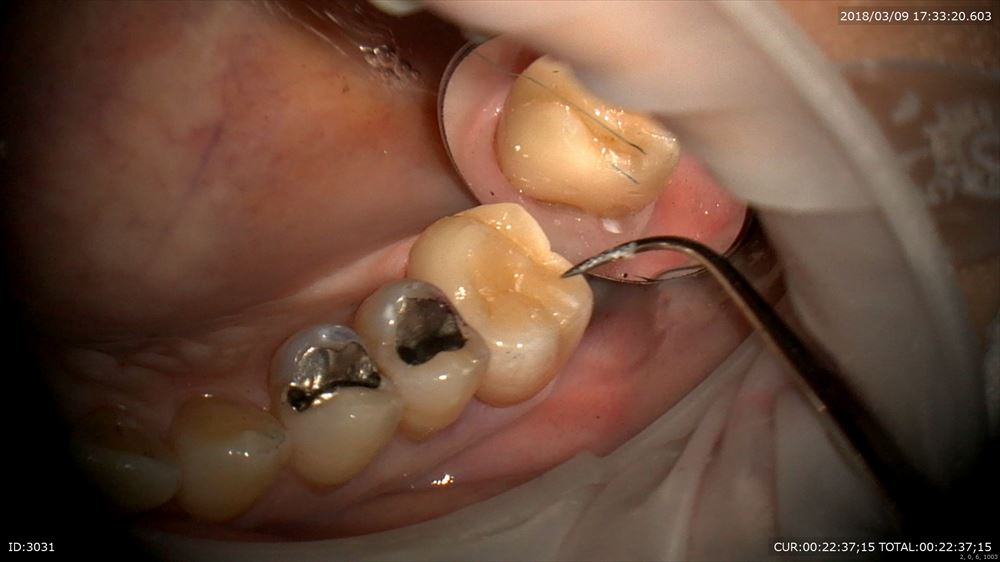

かみ合わせを見て

OK

フィットは寸分の狂いもないです。